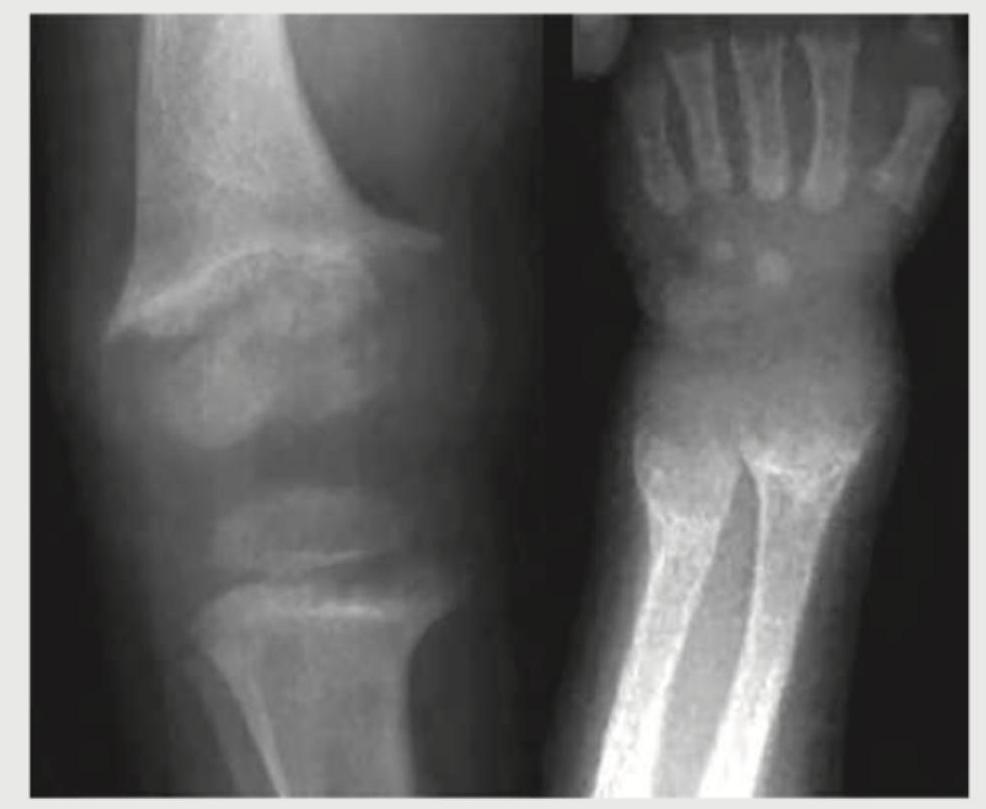

The CT head of this infant with macrocephaly shows:

Explanation: ***Dandy-Walker syndrome*** - The image shows a **markedly enlarged posterior fossa** with a **cystic dilatation** that communicates with the fourth ventricle (indicated by arrows on the axial scan). There is also **hypoplasia of the cerebellar vermis** and **hydrocephalus**, characteristic features of Dandy-Walker syndrome. - This condition is a congenital brain malformation affecting the cerebellum and the fluid-filled spaces around it, leading to symptoms like macrocephaly due to hydrocephalus. *Aqueductal stenosis* - Aqueductal stenosis would primarily cause **dilatation of the lateral and third ventricles**, with a normal-sized fourth ventricle due to the blockage. - It would not typically present with the characteristic large posterior fossa cyst and cerebellar vermian hypoplasia seen here. *Tubercular meningitis* - Tubercular meningitis on imaging typically shows **basal meningeal enhancement**, hydrocephalus, and sometimes infarctions or tuberculomas. - It does not present with a primary cerebellum malformation or a large posterior fossa cyst as demonstrated in the image. *Neurocysticercosis* - Neurocysticercosis involves parasitic cysts (larval stage of *Taenia solium*) in the brain parenchyma, subarachnoid space, or ventricles, often seen as **cystic lesions with a scolex**. - While it can cause hydrocephalus if cysts block CSF flow, it does not involve the specific malformations of the posterior fossa and cerebellum seen in Dandy-Walker syndrome.